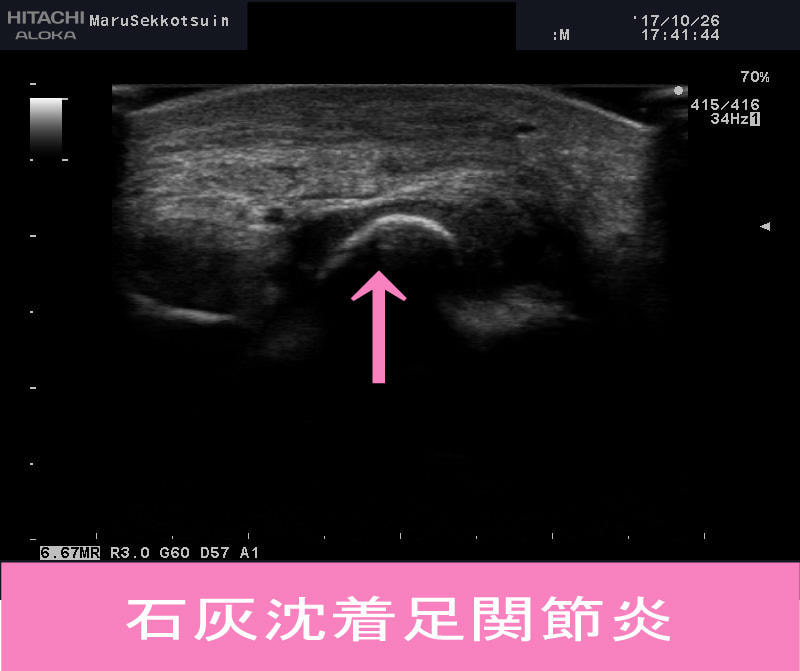

石灰沈着性足関節炎

そこでエコー検査(超音波画像観察装置)の出番です。

しっかり確認してみますと、やはり石灰像が確認できました。

石灰沈着性足関節炎.jpg